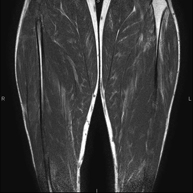

Exploració per estudiar la musculatura i dels tendons que s'originen en aquest nivell, com els tendons isquiotibials, lesió sovint en esportistes. La durada aproximada és de 16 minuts. No empra radiació ionitzant. - RM de Cuixa

Exploració ideal per estudiar les lesions en músculs isquiotibials i quàdriceps, sovint lesionats en esportistes. També permet una bona valoració de tendons i de nervis perifèrics. La durada aproximada és de 20 minuts. No utilitza radiació ionitzan. - RM de Genoll